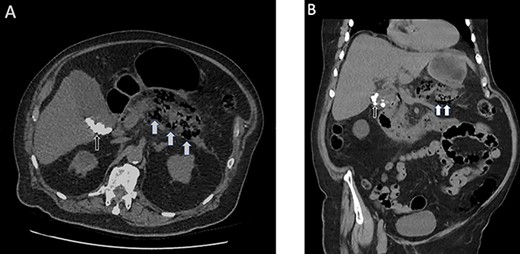

He was managed conservatively making minimal clinical progress and on day 3 developed a significant elevation of his inflammatory markers: C-reactive protein (CRP) >500, and WCC, 20. He had an associated acute kidney injury. His abdominal distension had increased with persistent vomiting. He progressed to have a non-contrast CT scan of the abdomen and pelvis that demonstrated extensive peripancreatic inflammatory change and interstitial air in the pancreas with associated air in the biliary tree and gallbladder as demonstrated in Fig. 1.

(A) Axial non-contrast CT scan of the abdomen and pelvis highlighting the interstitial air within the pancreas (white arrows) and multiple calcified gallstones within the gallbladder (black arrows). (B) Coronal view of the same scan.